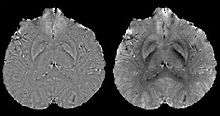

Calculation Of Susceptibility through Multiple Orientation Sampling (COSMOS)[11][12]

COSMOS solves the inverse problem by oversampling from multiple orientations.[11] COSMOS utilizes the fact that the zero cone surface in the Fourier domain is fixed at the magic angle with respect to the B₀ field. Therefore, if an object is rotated with respect to the B₀ field, then in the object's frame, the B₀ field is rotated and thus the cone. Consequently, data that cannot be calculated due to the cone becomes available at the new orientations.

COSMOS assumes a model-free susceptibility distribution and keeps full fidelity to the measured data. This method has been validated extensively in in vitro, ex vivo and phantom experiments. Quantitative susceptibility maps obtained from in vivo human brain imaging also showed high degree of agreement with previous knowledge about brain anatomy. Three orientations are generally required for COSMOS, limiting the practicality for clinical applications. However, it may serve as a reference standard when available for calibrating other techniques.